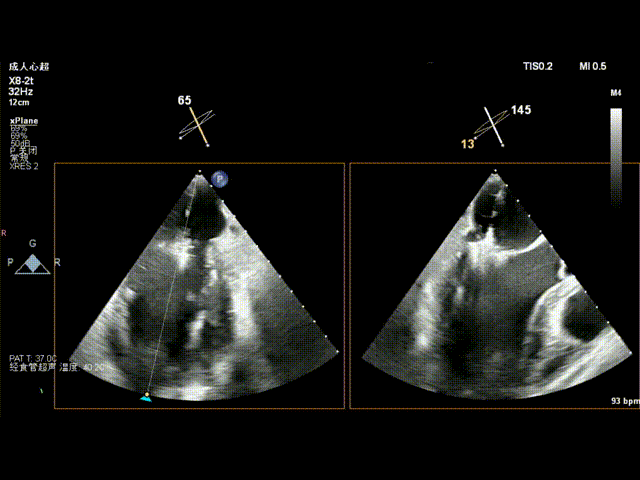

术前食道超声示: 二尖瓣重度反流,1区脱垂并累及外交界。

术前食道超声-3D